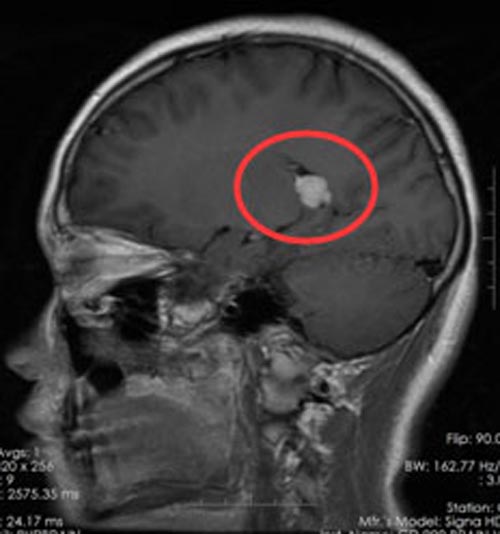

我院头颅MR检查提示:“1.右侧侧脑室后角内占位性病变,考虑为偏良性肿瘤性病变,建议补充DWI,MR增强+MRS,以求进一步明确病变性质;2.鼻咽顶后壁软组织稍增厚;3.蝶窦轻度炎症。”肿瘤有占位效应,边界清楚,呈圆形、类圆形或不规则分叶形,多数瘤周存在一环形或弧形的低信号区,强化或增强后呈均匀明显强化。

考虑脑膜瘤可能性大,而且有手术指证,建议小朱进行手术。妈妈在自责之后,也积极地同意手术治疗。完善术前准备后,由综合神经外科鲁明副院长主刀在“全麻神经导航下球囊辅助右侧侧脑室后角内占位病变切除术”。术中仔细保护脑组织和血管,镜下全切肿物,术中出血仅100ml,未输血。

小朱麻醉清醒后神志清楚,生命征平稳,言语对答切题,自主体位,体查合作,四肢肌力Ⅴ级。病理检查结果示:右侧侧脑室后角肿瘤由长梭形成纤维细胞样细胞构成,肿瘤细胞排列成束状或编织状,核梭形,具有异型性,诊断为右侧侧脑室后角非典型脑膜瘤,WHO II级。